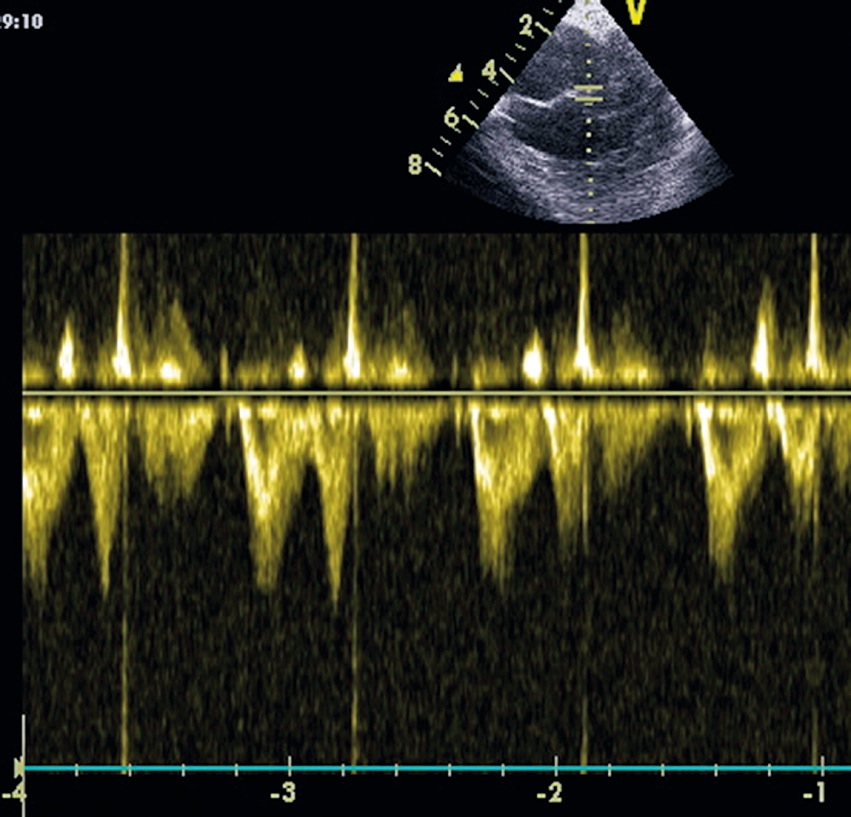

La disfunción diastólica es un cambio propio del envejecimiento 1 , 2 ; a nivel del miocardio los miocitos son reemplazados por fibroblastos que producen colágeno y fibrosis intersticial. Esto, en conjunto con la pérdida de miocitos por necrosis, provoca que el ventrículo izquierdo se vuelva rígido y menos complaciente, de manera que el llene diastólico se ve dificultado, pasando a tomar más importancia la contracción de la aurícula izquierda para conseguir el llene ventricular. En el miocardio, a nivel intracelular, se produce una disfunción de la bomba ATPasa del retículo sarcoplásmico que controla la recaptación de Ca++, esto lleva a una prolongación de la relajación iso volúmica. La disfunción diastólica, con el método de Doppler transmitral, tiene un patrón ecocardiográfico caracterizado por una mayor preponderancia de la onda A (referida a la contracción auricular), en relación a la onda E (onda de llenado rápido) (Figura 2).

Figura 2 Doppler transmitral. Onda E y Onda A en disfunción diastólica (Gentileza Dr. Renato Chacón A. Anestesiología Clínica Dávila).